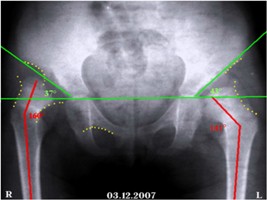

Клинический пример. Больная К., 4 года, поступила в отделение детской ортопедии и травма-тологии 03.12.2007. Поступила с жалобами на боли, хромату и ограничения движений. Лечения до поступления не получала. На момент поступления имелась следующая рентгенологическая картина (рис. 1а,б).

а б

Рис. 1а,б. Рентгенограмма таза. Врожденный вывих правого бедра, подвывих левого. Переднезадняя проекция

- а - нейтральная позиция. Красным указанны шеечно-диафизарные углы до операции (правый – 1600 и левый – 1410). Зеленым указаны ацетабулярные углы до операции (правый – 370 и левый – 430).

- б - Отведение и внутренняя ротация. Красным указанны шеечно- диафизарные углы до операции (правый – 1400 и левый – 1360). Угол патологической антиторсии справа–650, слева – 300.